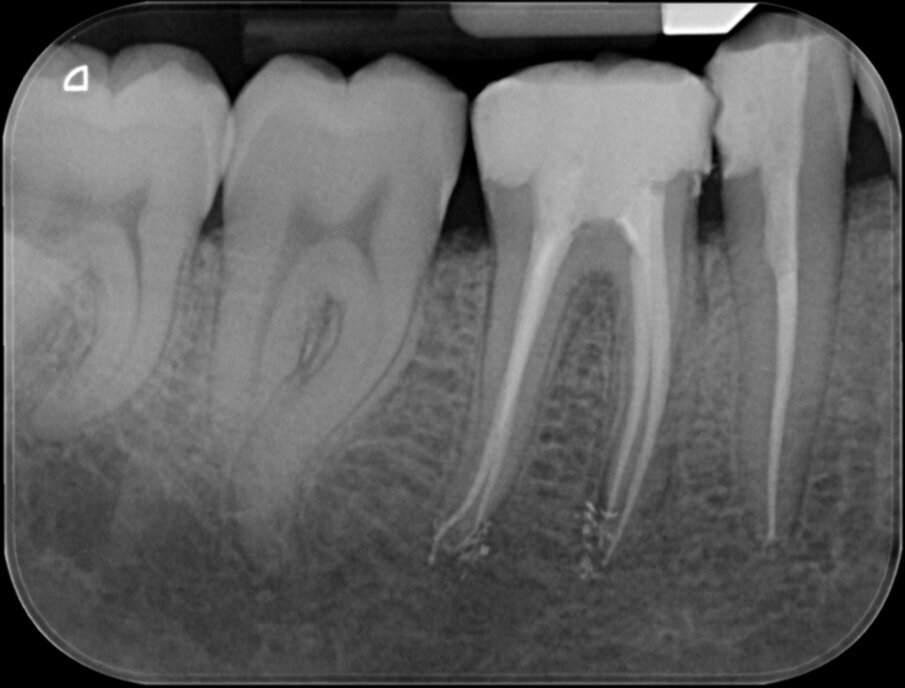

De eindfoto’s stemmen tot optimisme. Röntgenologisch lijkt voldaan aan al de eisen die Schilder aan de vorm van geprepareerde kanalen stelde.

Er lijkt sprake van een gevuld systeem (afbeelding 3 en 4). De puffs in de laatste paar millimeter hebben geen klinische betekenis, maar zijn een normaal bijverschijnsel bij het obtureren van kanalen met een hydraulische obturatiemethode, gebruik makend van warme guttapercha. Hier kozen we voor Thermafil, wat een uitstekende reputatie heeft en de preferente vulmethode is van veel eminente clinici, zoals Buchanan en Ruddle. Vol vertrouwen presenteren we de resultaten aan de patiënt en we schrijven een brief aan de verwijzend tandarts dat het vervaardigen van een kroon nu kan geschieden zonder onaanvaardbare risico’s.

Vier jaar later bezoekt de patiënt wederom op verwijzing onze praktijk. Hij ondervindt wat ongemak van element 46 waar de tandarts 3 jaar geleden een kroon op heeft gemaakt. Bij kauwen is het element iets pijnlijk, iets wat hem sinds twee maanden opgevallen is. Afbeelding 5, 6 en 7 kunnen bevestigen wat de oorzaak is: Een opspelende laesie van endodontische origine (LEO) aan de mesio-buccale radix. Bittere teleurstelling aan onze zijde en een verdrietige patiënt.